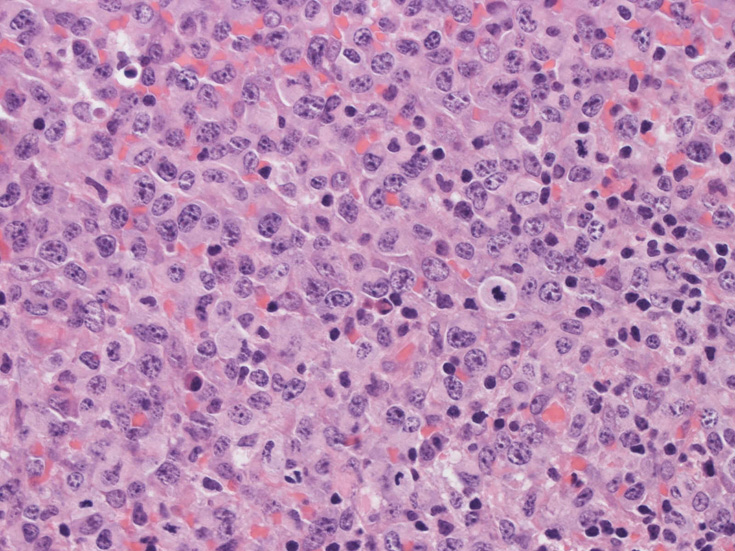

リンパ節, 増殖腫瘍細胞の病理所見

腹膜脂肪組織内から生検されたリンパ節は基本構造を失っている。低倍率のHE所見では異型細胞が不鮮明な結節構造を形成して増殖している。一次リンパ濾胞を腫瘍細胞が置換しているように見える所見がある。

高倍率x400では, 増殖細胞はcentroblastに似て複数の明瞭な核小体をもった淡明な大型類円ないし卵円形核を持っている。核分裂像が多い。この症例では多型はめだたない。典型的な腎臓型のくびれた核を持つ細胞などはない。ALKの形態的variant症例と考えられるが, 化学療法後の再発による影響も否定できない。